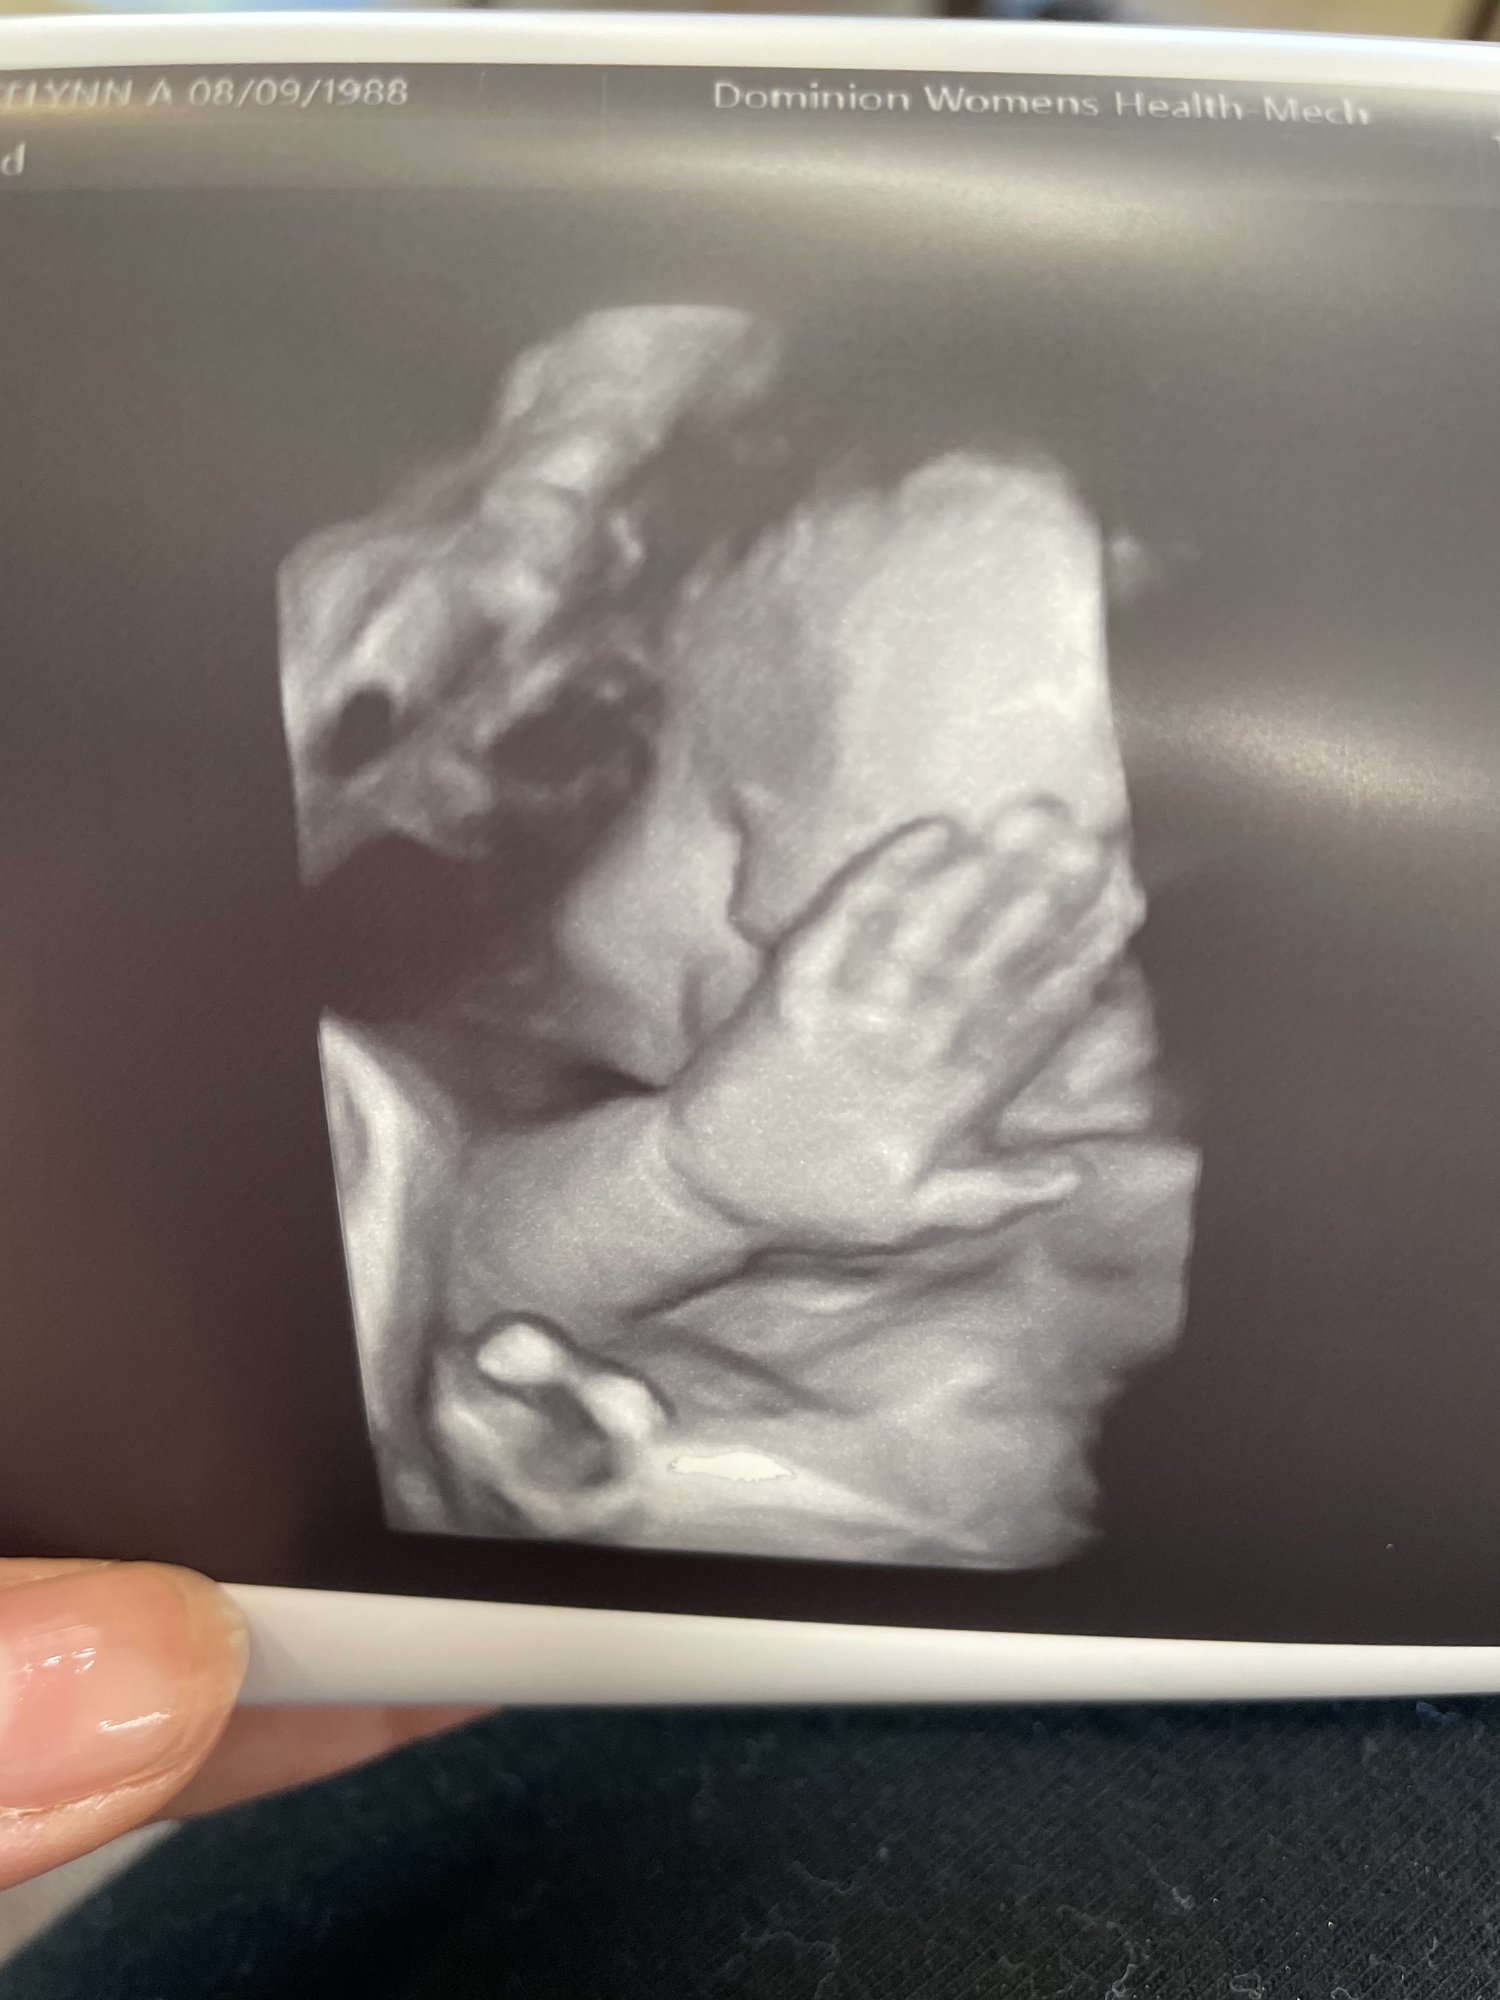

@alexxajams they only tried the 3D for a few minutes, and I think only to try to get a good picture for us. Not sure my regular OB even has a 3D one in their office